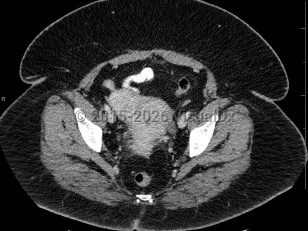

Uterine fibroids

Fibroids are often asymptomatic and may be only first noted incidentally on imaging done for other reasons, but patients can also present with abnormal bleeding, infertility, painful intercourse, constipation, increased pelvic or bladder pressure, urinary frequency, or rectal pressure.